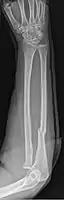

- Galeazzi fracture - not a fracture of the ulna but a displaced fracture of the radius accompanied by a dislocation of the ulna at the wrist, where the radius and ulna come together.[2]

- Galeazzi facture (displaced fracture of the radius)

When there is a displaced fracture and also when the radioulnar joints are involved an operation is often performed, using either flexible rods or screws and plates in order to reduce the fracture and immobilise the bone.[2]